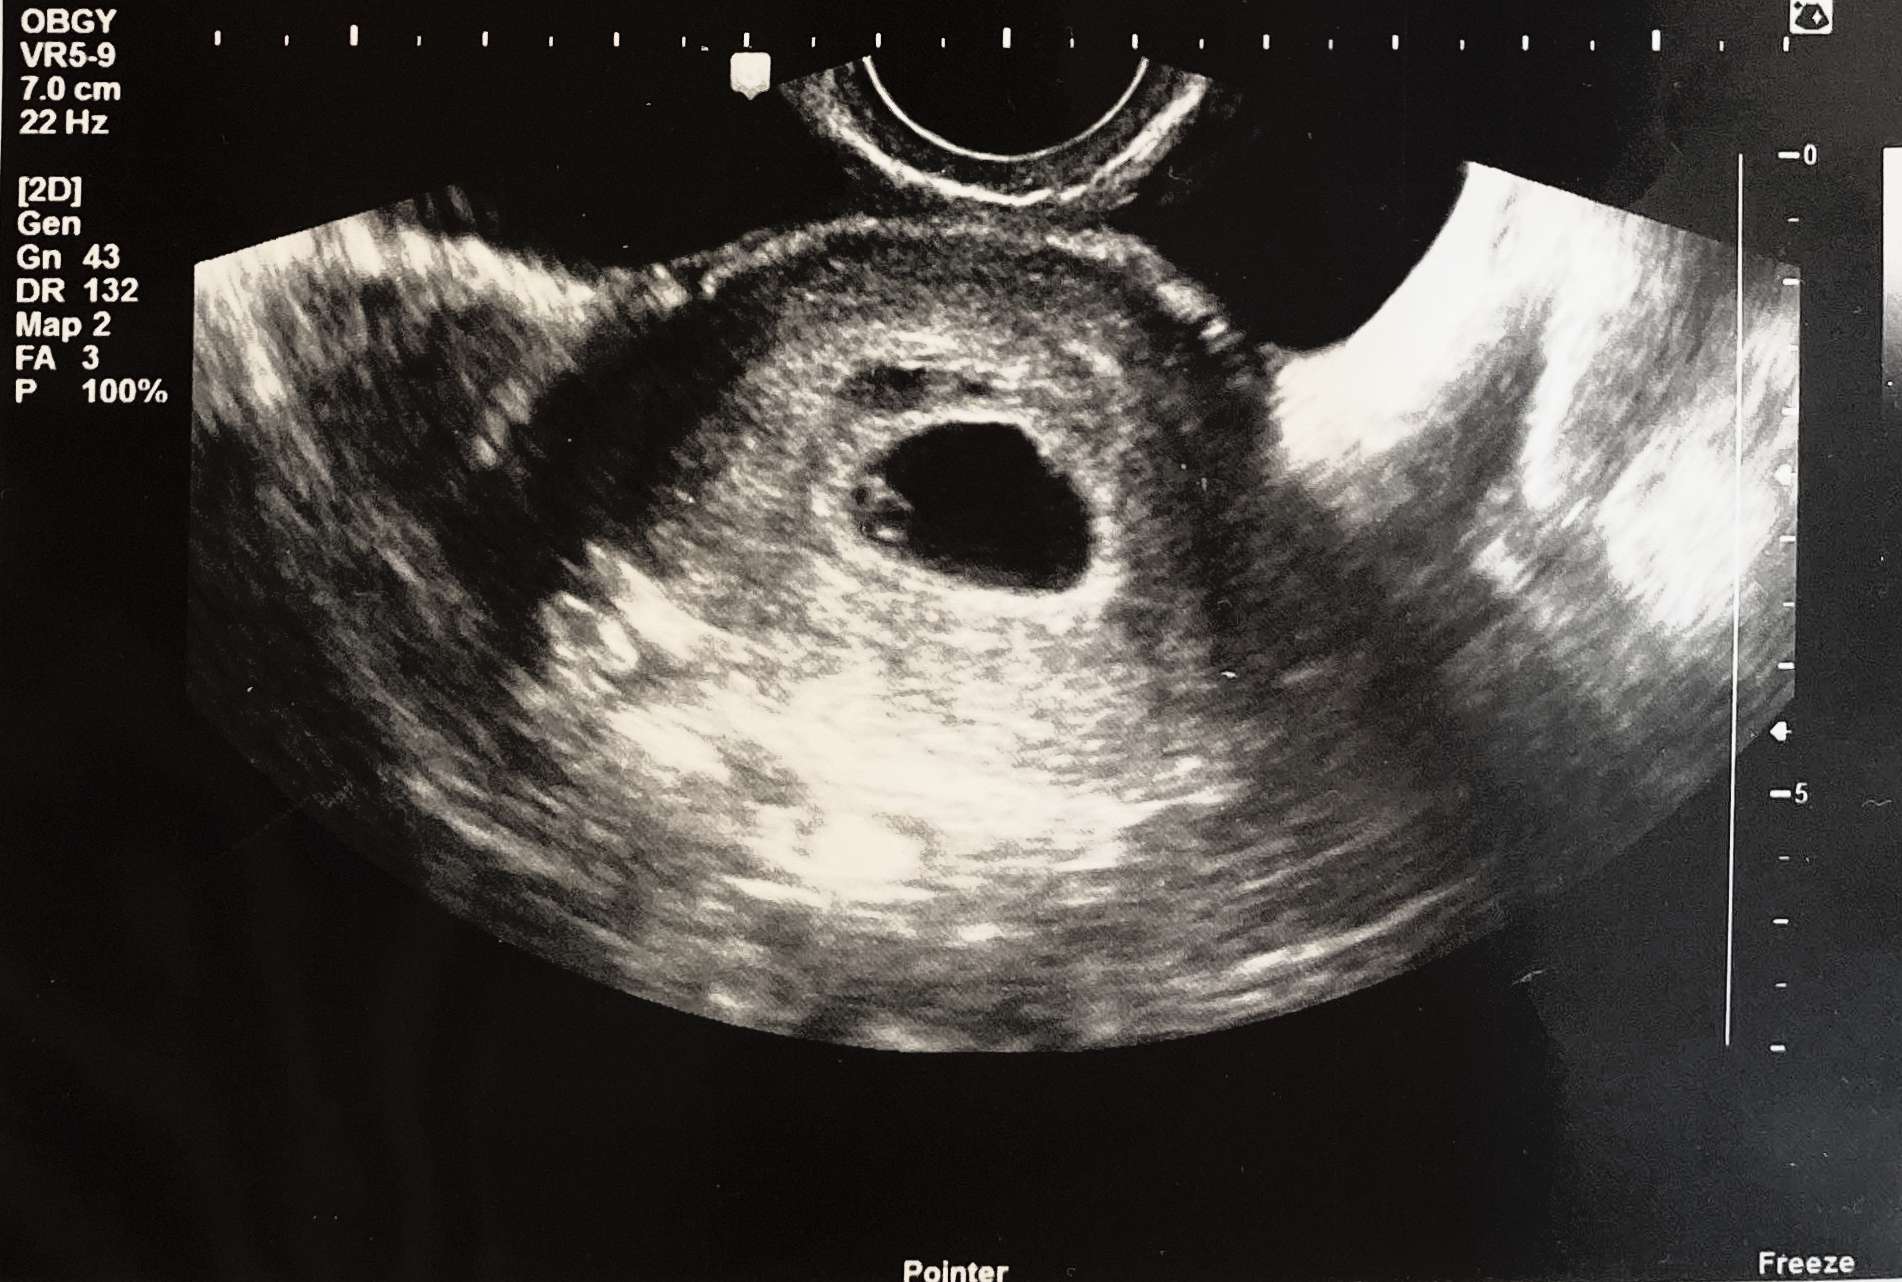

내 1순위 걱정은 바로 아기집에 아기가 있을지 여부였다.

계류 유산 이야기를 주워듣고 보고 하는 바람에 내 두려움이 너무 커졌던 탓이다.

다행히도 난황도 생겨있었고 아기 심장이 반짝반짝하는 것까지 보았다.

아기는 있었다.

아직 너무 작아서 심장소리까지는 안 들려주셨지만,

그래도 아기가 있는지는 확인을 했다.

그런데 피고임이 좀 있어서 선생님이 유산방지제 주사를 처방해 주셨고,

아기집이 좀 작다고 해서 또 다른 걱정이 시작되었다.